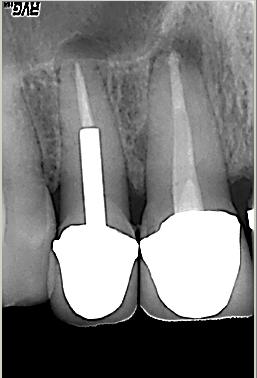

Röntgenologischer Ausgangsbefund im September. 2002 mit alio loco durchgeführter WF. Beide Wurzeln weisen eine apikale Parodontitis auf. Auch in der Furkation ist eine deutliche Resorption zu erkennen. Der Patient hat massive Schmerzen und einen stark herabgesetzten Allgemeinzustand

Röntgenmeßaufnahme

Röntgenmeßaufnahme nach vorgängig durchgeführter endometrischer Längenbestimmung. Nach der ersten Behandlung trat zunächst eine Verbesserung der Symptomatik auf. Nach ca. einer Woche kam es zu einer akuten Exacerbation mit lingualer Abszeßbildung. Der Abszeß wurde inzidiert